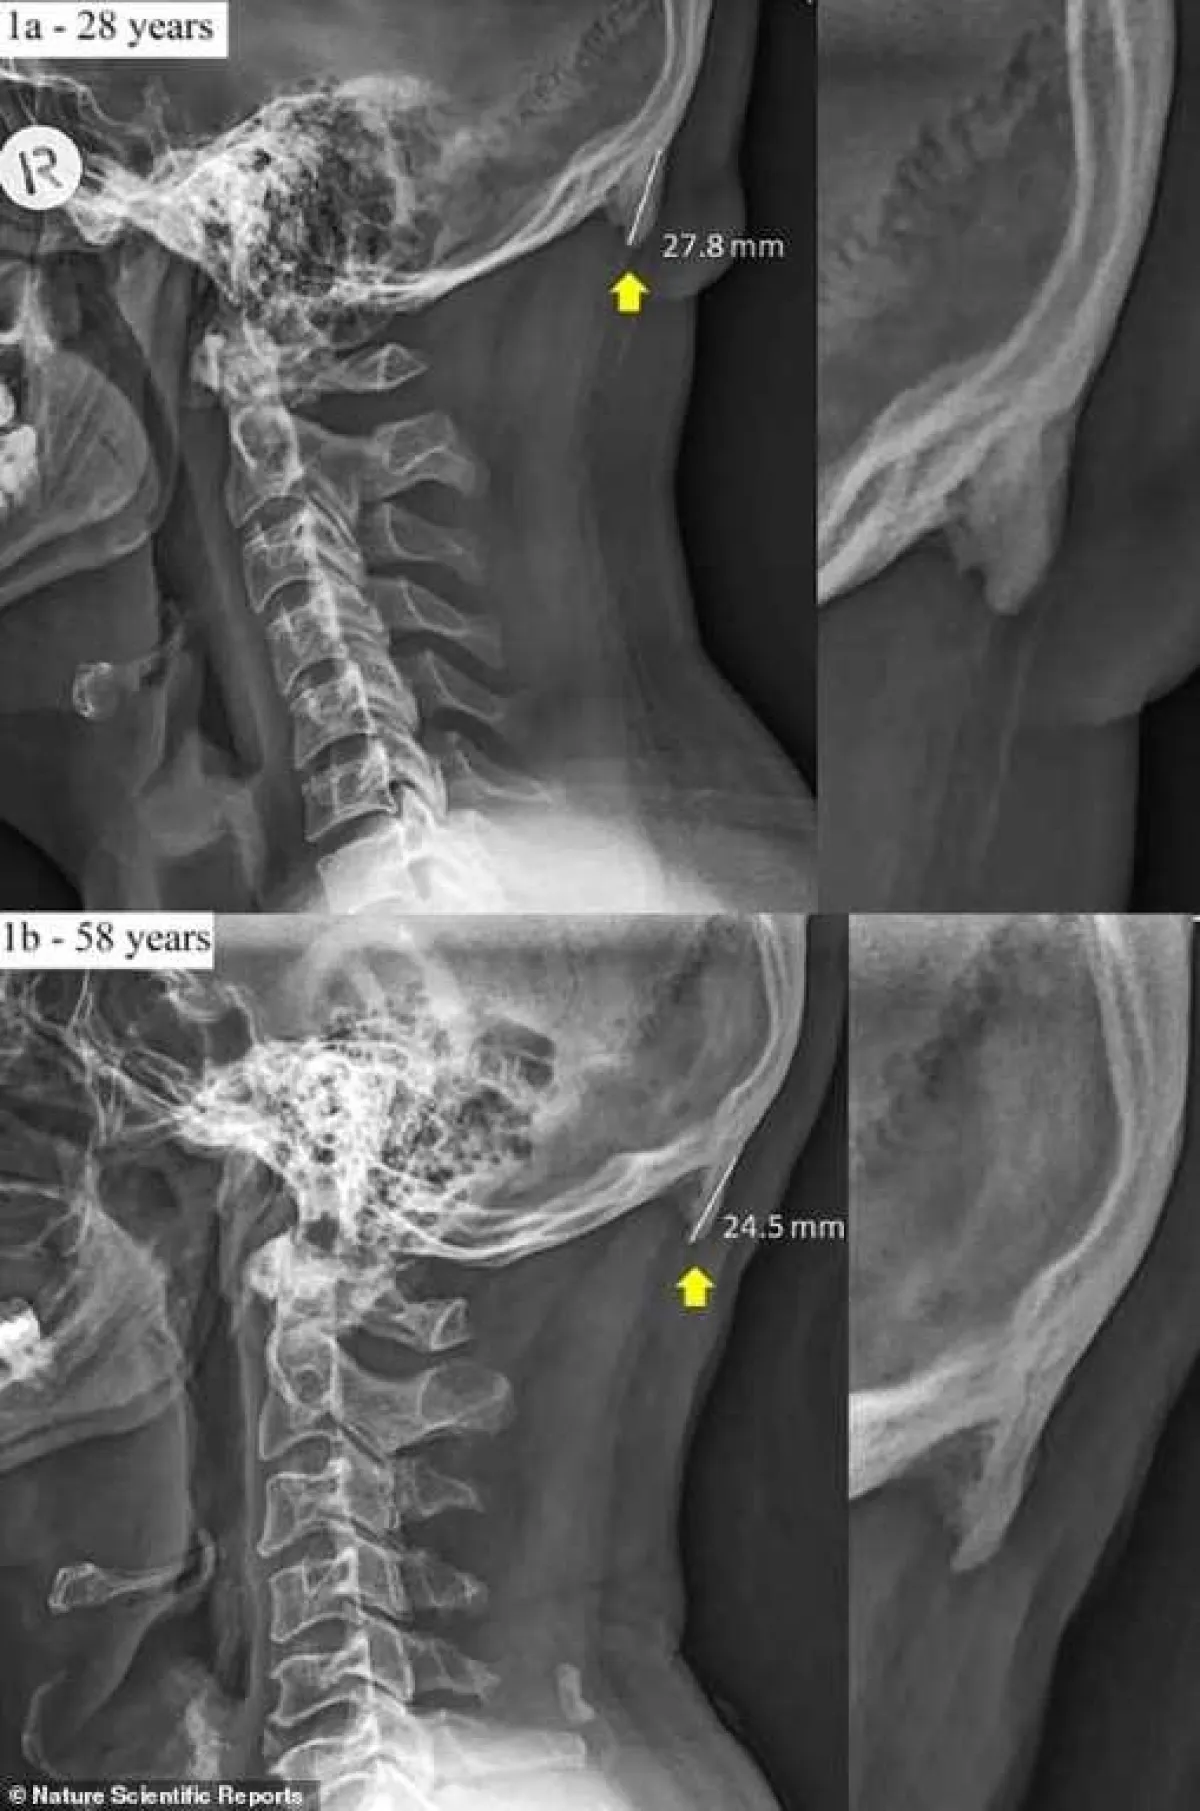

ووفقاً لما نقله موقع «روسيا اليوم»، عن صحيفة الـ«ديلي ميل» البريطانية، فإن العلماء في جامعة «صن شاين كوست»، في مقاطعة «كوينزلاند» الأسترالية، أشاروا خلال دراسة جديدة أجروها في الفترات الماضية، إلى أن ما يطلق عليه «النتوءات القذالية الخارجية» المتضخمة في قاعدة الجمجمة، تنمو بشكل متزايد لدى هؤلاء الأشخاص الذين يقضون أوقاتاً طويلة مع أجهزتهم الذكية، مشيرين إلى أن متوسط حجم هذه النتوءات يبلغ ما نحوه 2. 6 سنتيمتر.

وتابع علماء الجامعة الأسترالية، أننا في الوقت الحاضر، قد نكون قادرين على الإحساس بهذه الكتل العظمية عبر تلمسها بأصابعنا أو رؤيتها لدى الأشخاص الذين يعانون من الصلع. وأكدوا أن من هم أصغر عمراً، بإمكانهم أن يطوروا هذه «الطفرات» بشكل أسرع ممن هم في عمر أكبر. إذ إن الأبحاث أظهرت أن هذه الطفرات تنتشر بشكل أكبر لدى الأشخاص الذين تتراوح أعمارهم ما بين الـ 18 إلى 30 عاماً.

وتابعت الـ«ديلي ميل»، أنه بحسب تقرير نشرته شبكة الـ«بي بي سي فيوتشر BBC Future» البريطانية. فقد قام علماء جامعة «صن شاين كوست»، بإجراء العديد من الأبحاث المنفصلة حول هذه الظاهرة، وفحصوا خلال هذه الأبحاث ما يقارب الـ1000 جمحمة لأشخاص تتراوح أعمارهم ما بين الـ18 عاماً والـ 86 عاماً، حتى تمكنوا من الوصول إلى هذه النتائج.